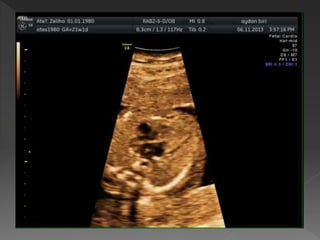

 Fetusu doğru

değerlendirebilmek için

nasıl durduğunu bilmek

önemlidir

 Proba göre omurga;

yukarı, arkada ya da

lateralde

 Mide ve kalbin sol da

olduğunu teyit